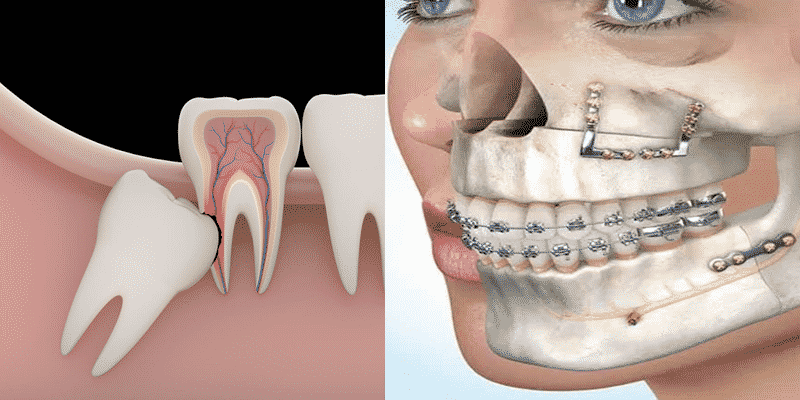

ORTOPEDIA

La finalidad de la ortopedia, es la de normalizar tanto la forma, como el tamaño de los maxilares, que al estar alterados presentan mal alineamiento de los dientes en niños.

CIRUGÍA ORAL Y MAXILOFACIAL

Se encarga de diagnosticar y tratar quirúrgicamente las enfermedades, traumas, extracción de cordales, restos radiculares, drenaje de abscesos, dientes incluidos. Preparar el terreno protesico.